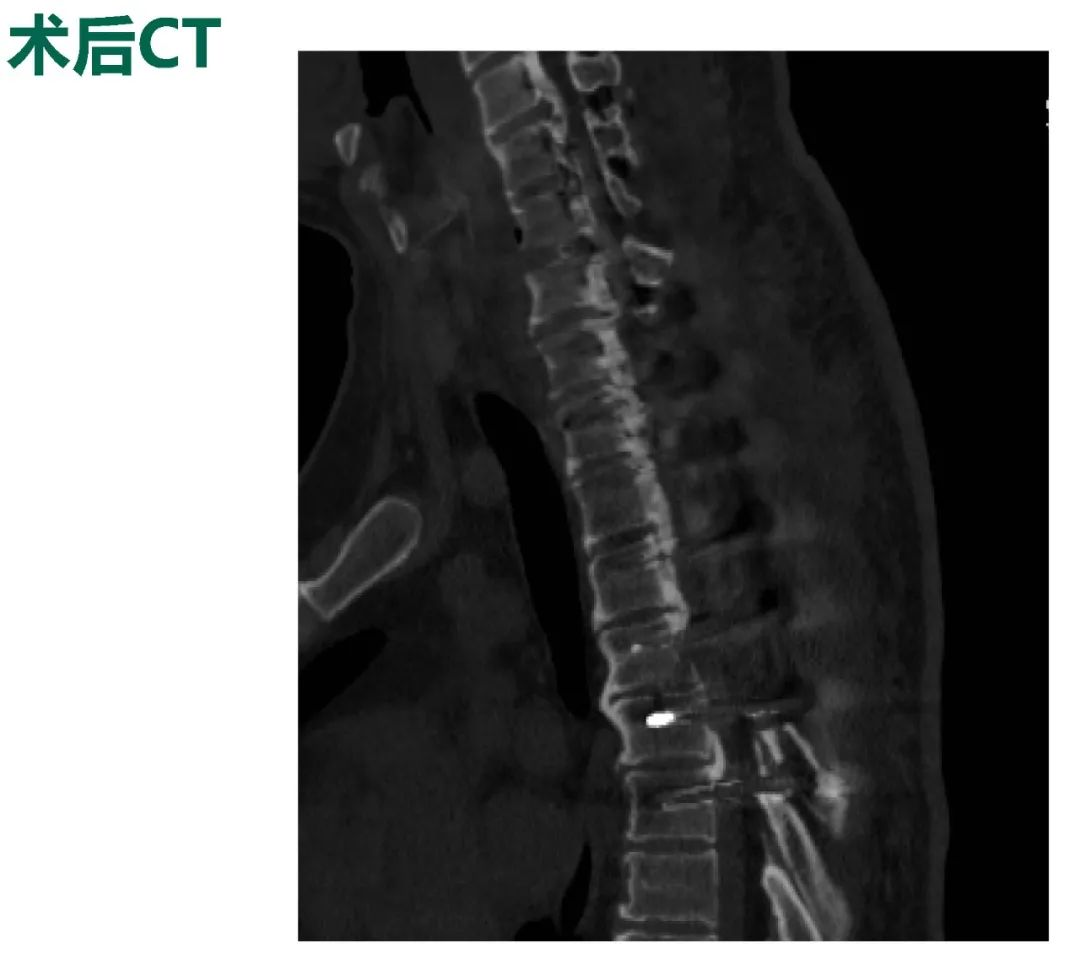

Thoracic spinal stenosis decompression(T2-T3)

术后3个月: